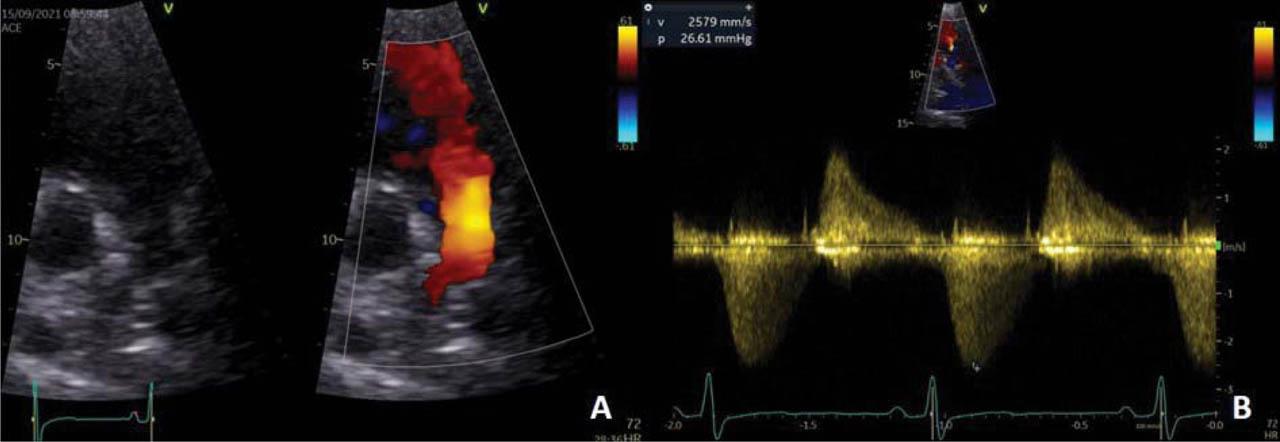

Figure 2

Transthoracic echocardiography modified parasternal short axis view. (A) 2D and color Doppler examination: large colour-flow pulmonary regurgitation jet width suggestive for severe pulmonary regurgitation. (B) CW Doppler examination: dense, steep deceleration of pulmonary regurgitation jet CW signal, with a pressure half time of 98 ms, suggestive for severe pulmonary regurgitation; peak antegrade velocity 2.6 m/s, peak antegrade gradient 26 mmHg, suggestive for large residual pulmonary stenosis.